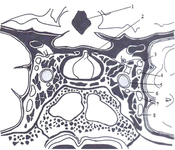

Anatomia do seio cavernoso: (1) terceiro ventrículo, (2) hipófise, (3) nervo oculomotor, (4) nervo troclear, (5) artéria carótida interna, (6) nervo abducente, (7) ramo oftálmico do nervo trigêmeo, e (8) ramo maxilar do nervo trigêmeo

Visvanathan V, et al. Revisão de uma lição clínica importante: manifestações oculares da trombrose do seio cavernoso. BMJ Case Rep. 2010; doi:10.1136. Usado com permissão